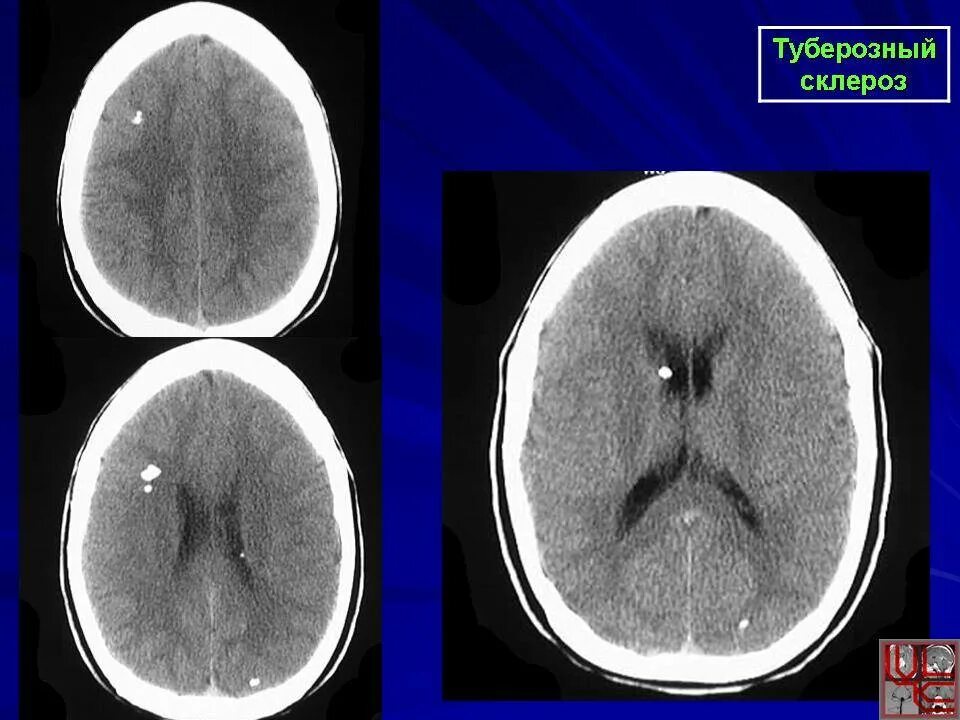

Туберкулезный склероз